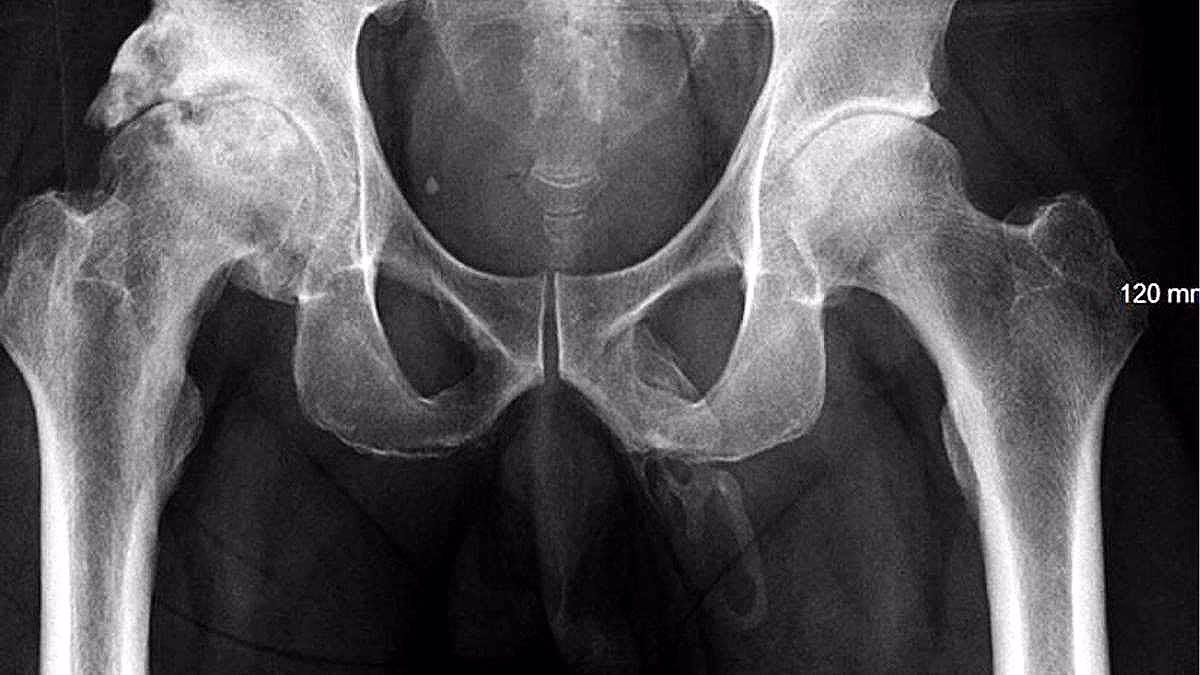

The medical team decided to take X-rays of his lower body to rule out fractures. What they discovered was astonishing - a bone in the region of his private part. This led to the diagnosis of a very rare condition known as Penile Ossification.

This condition causes calcium to deposit within the soft tissues of the organ, leading to abnormal bone formation. When asked if he wanted further treatment, the man declined any more tests or interventions. Doctors explained that treatment typically involves administering painkillers.

The condition can be managed with shock wave therapy, using sonic waves to break down the bone into smaller pieces. To date, medical literature has documented only 40 such cases, and these rare occurrences are often associated with Peyronie's Disease.